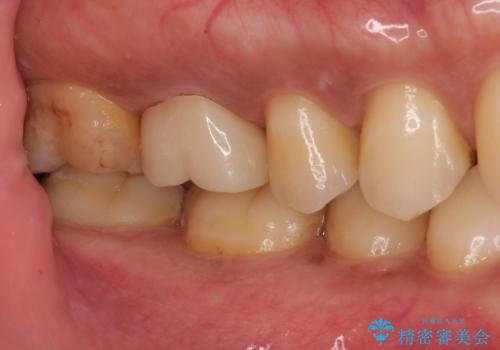

- セラミックの詰め物が割れたとのことで来院された患者様です。現在に至るまで二度セラミックの詰めもの(セラミックインレー)が割れていて、噛み合わせも強い方なのでフルジルコニアクラウンとゴールドクラウン(PGAクラウン)を治療方法としてご提案しました。

患者様と相談した結果、強度と見た目の良いフルジルコニアクラウンで治療していくことになりました。

拡大鏡視野下で保険のプラスチック(コンポジットレジン)、虫歯を除去し、フルジルコニアクラウン、に適した形にしました。

前から6番目の歯の頬側は個人差はありますが笑った時に見えるのでセラミックによる治療を行うと非常に審美的です。

見た目、機能面ともに満足していただけました。